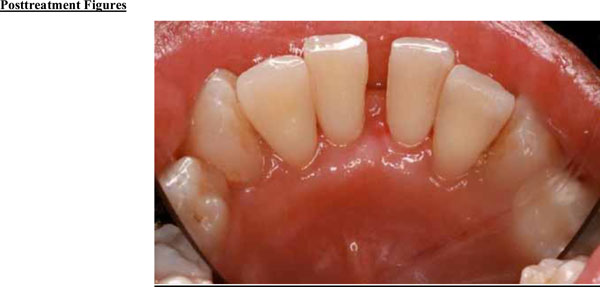

Fig. (3a).

Significant improvements in tissue color, contour, and consistency are apparent at 6 months after removal of the fibroma.

Fig. (3b).

Significant improvement in bone quantity and a reduction in the separation of teeth 24 and 25 are evident on the 6-month posttreatment radiograph.

The tumor was successfully removed, and to rebuild the hard and soft tissue that had been compromised as a result of tumor expansion, periodontal regenerative therapy was offered. The patient accepted the therapy and the surgical site was bone grafted, with excellent results (Figs. 3a and 3b). Preventive measures were taken before the tumor was able to spread further, which might have led to severe bone loss and possible complications.